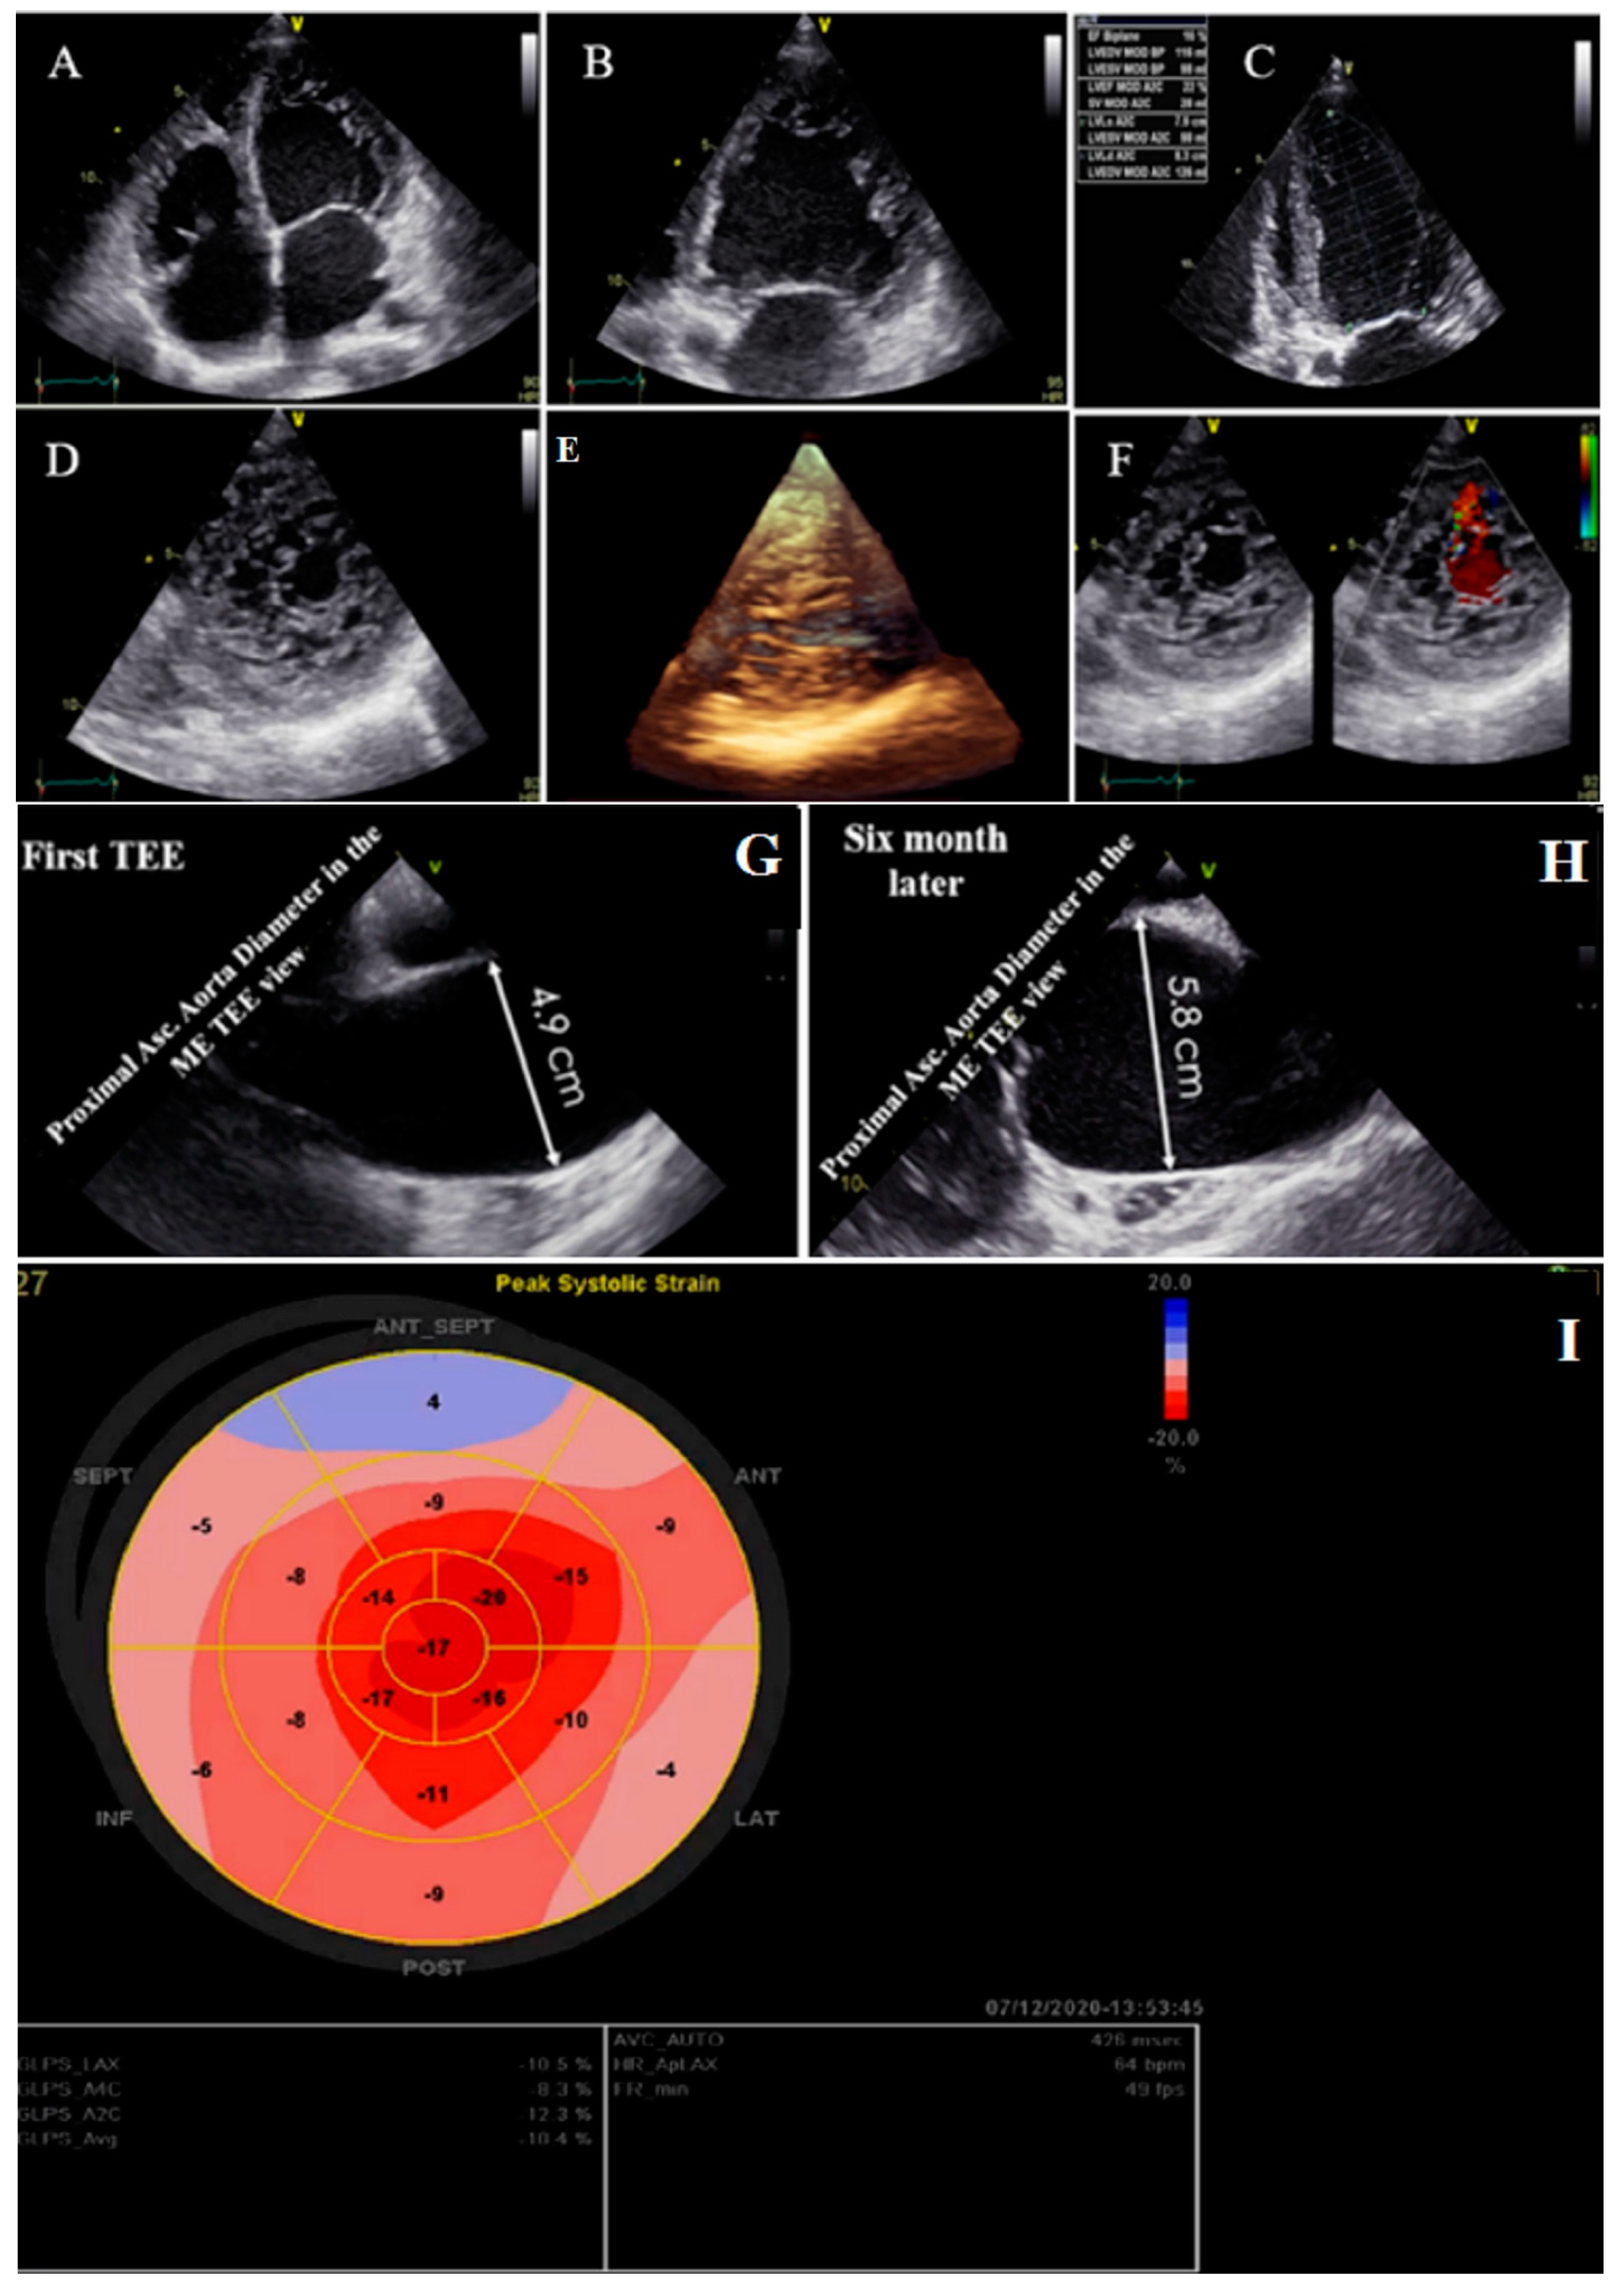

2.5. Case #5. NCLV and Arteria Lusoria

| 5 | F | 41 | Echocardiography after angiography | Positive family history for CAD | NCLV, LVEF = 55% | BAV and Arteria Lusoria | + | + | Nil, suggested being under cardiologist follow-up at home country | Did not refer for follow-up |